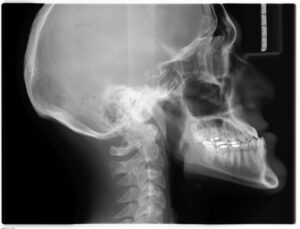

Røntgenundersøgelse

31 juli 2025